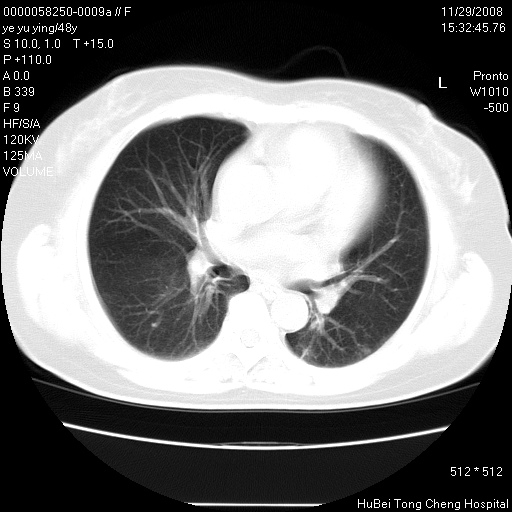

以下是引用huenhao在2008-11-29 22:11:00的发言:[br]脂肪肝,胆囊结石。左肺病灶建议定期复查。

以下是引用liuyue在2008-11-30 5:44:00的发言:[br]1.左肺病变,首先考虑感染性病变,转移待排;建议治疗后复查。[br]2.肝脏密度普遍减低,考虑与化疗有关。[br]3.胆囊结石.